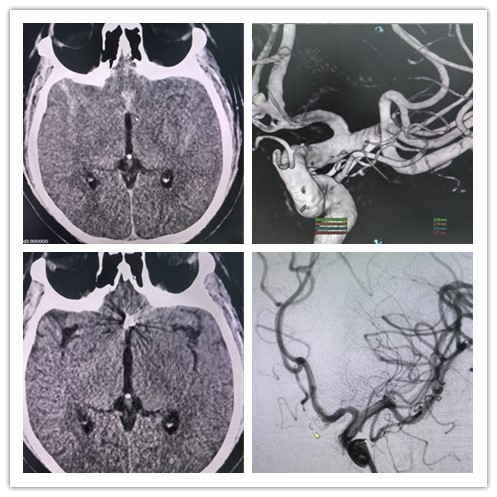

患者为38岁男性,因剧烈头痛伴喷射性呕吐3小时收住入院,积极完善相关检查后,结果显示为脑动脉瘤破裂致蛛网膜下腔出血。陇西县第一人民医院各部门积极协调,迅速开通脑卒中绿色通道,兰大二院神经外科帮扶队员刘吉星携手当地医院神经介入团队为患者成功实施了“支架辅助下颅内动脉瘤弹簧圈栓塞术”,精准完成破裂动脉瘤的血管内介入治疗。术后,通过规范化及个体化治疗,患者颅内出血恢复状况良好,各项生命体征平稳,未发生神经系统并发症。

术前术后对比图(左上为术前,其余为术后)